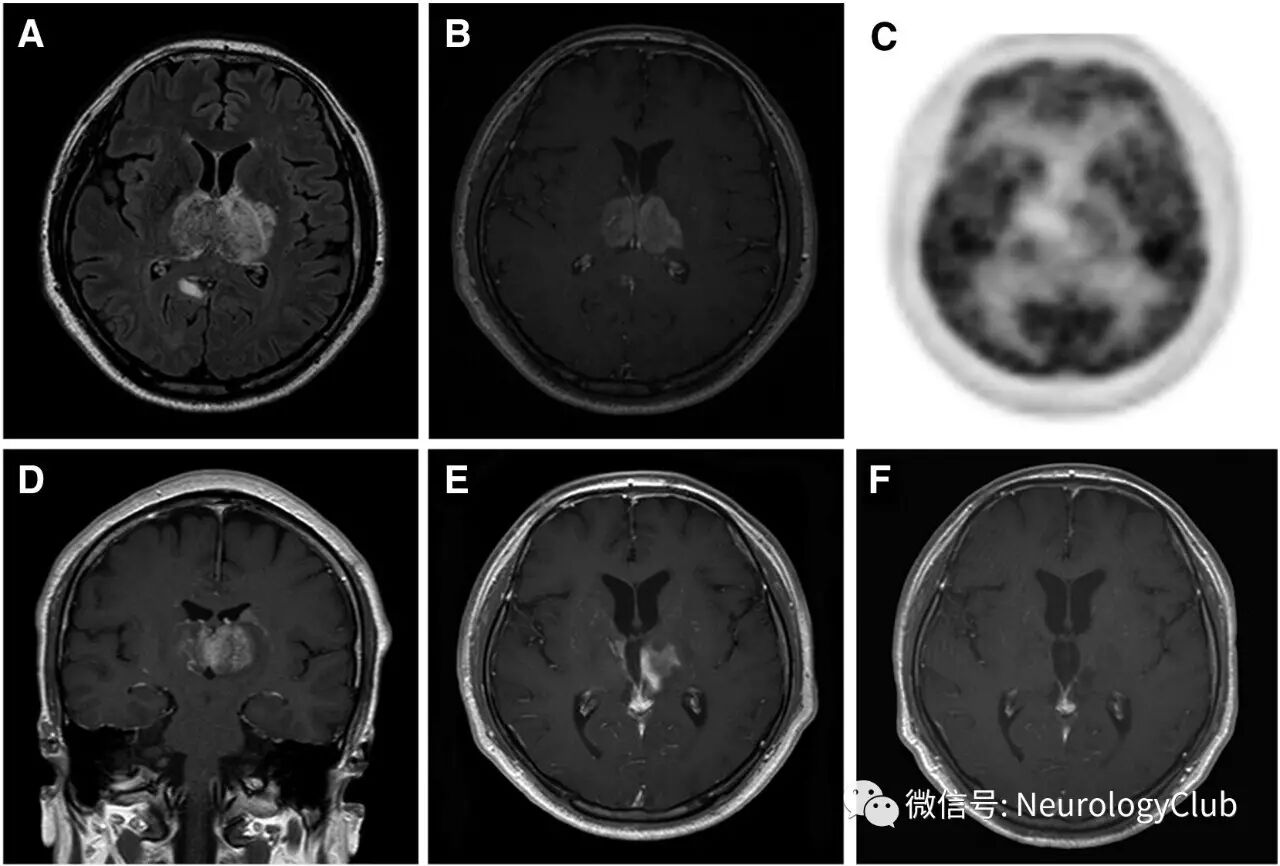

45岁男性,既往有高血压病史,表现为意识改变,2周前有流感样症状。神经精神评估提示注意力,记忆,视空间和额叶执行功能明显下降。韩国简明精神状态检查量表(K-MMSE)评分9/30。除轻度构音障碍外无其他神经功能缺失体征。精神病或情感症状不明显。血液学化验仅提示血沉稍升高(25mm/hr)。脑脊液检查有核细胞数正常,未见恶性肿瘤细胞,培养阴性。头颅MRI可见双侧丘脑T2/FLAIR高信号肿瘤样病灶,伴强化(图1A,B,D)。

(图:A-D:2013年1月检查;A:FLAIR;B,D:T1增强;MRI可见双侧丘脑强化肿瘤样病灶;C:FDG-PET可见双侧丘脑代谢轻微降低;E:2013年5月复查T1增强病灶范围缩小;F:2014年1月复查T1增强可见双侧丘脑信号基本正常

立体丁香活检未见恶性肿瘤证据,但存在多灶性梗死和出血,血管周围淋巴细胞浸润,一处血管官腔闭塞,提示原发性中枢神经系统血管炎。免疫组化染色CD3和CD20阳性。活检后PET检查提示双侧丘脑代谢轻度降低(图C)。患者接受糖皮质激素治疗并逐渐减量,同时予以其他对症处理。4月后复查头颅MRI可见病灶缩小。1年后双侧丘脑病灶基本消失。